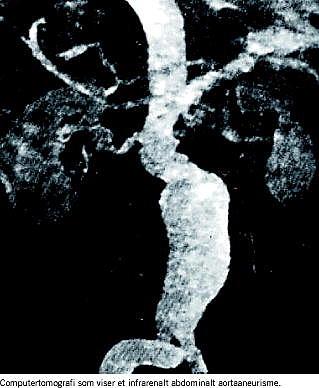

Abdominale aortaaneurismer (AAA) forekommer med stigende hyppighed i den ældre del af befolkningen, især hos mænd. Ruptur er forbundet med høj mortalitet, selv når akut kirurgi udføres. Af disse grunde har det flere gange været foreslået at indføre screening for AAA med henblik på tidlig opsporing og evt. profylaktisk kirurgisk indgriben. Om man skal foretrække operation frem for nøje observation afhænger af rupturrisikoen kontra operationsmortaliteten. Operationsmortaliteten kan registreres, men det er vanskeligere at undersøge rupturrisikoen.